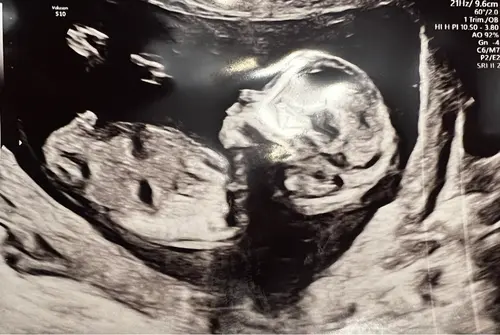

De nub is hier goed te zien. Denk boy maar ben niet zeker vanwege lighoudin ...

Dank voor je reactie! Het is een video opname, hier nog een paar screenshots.